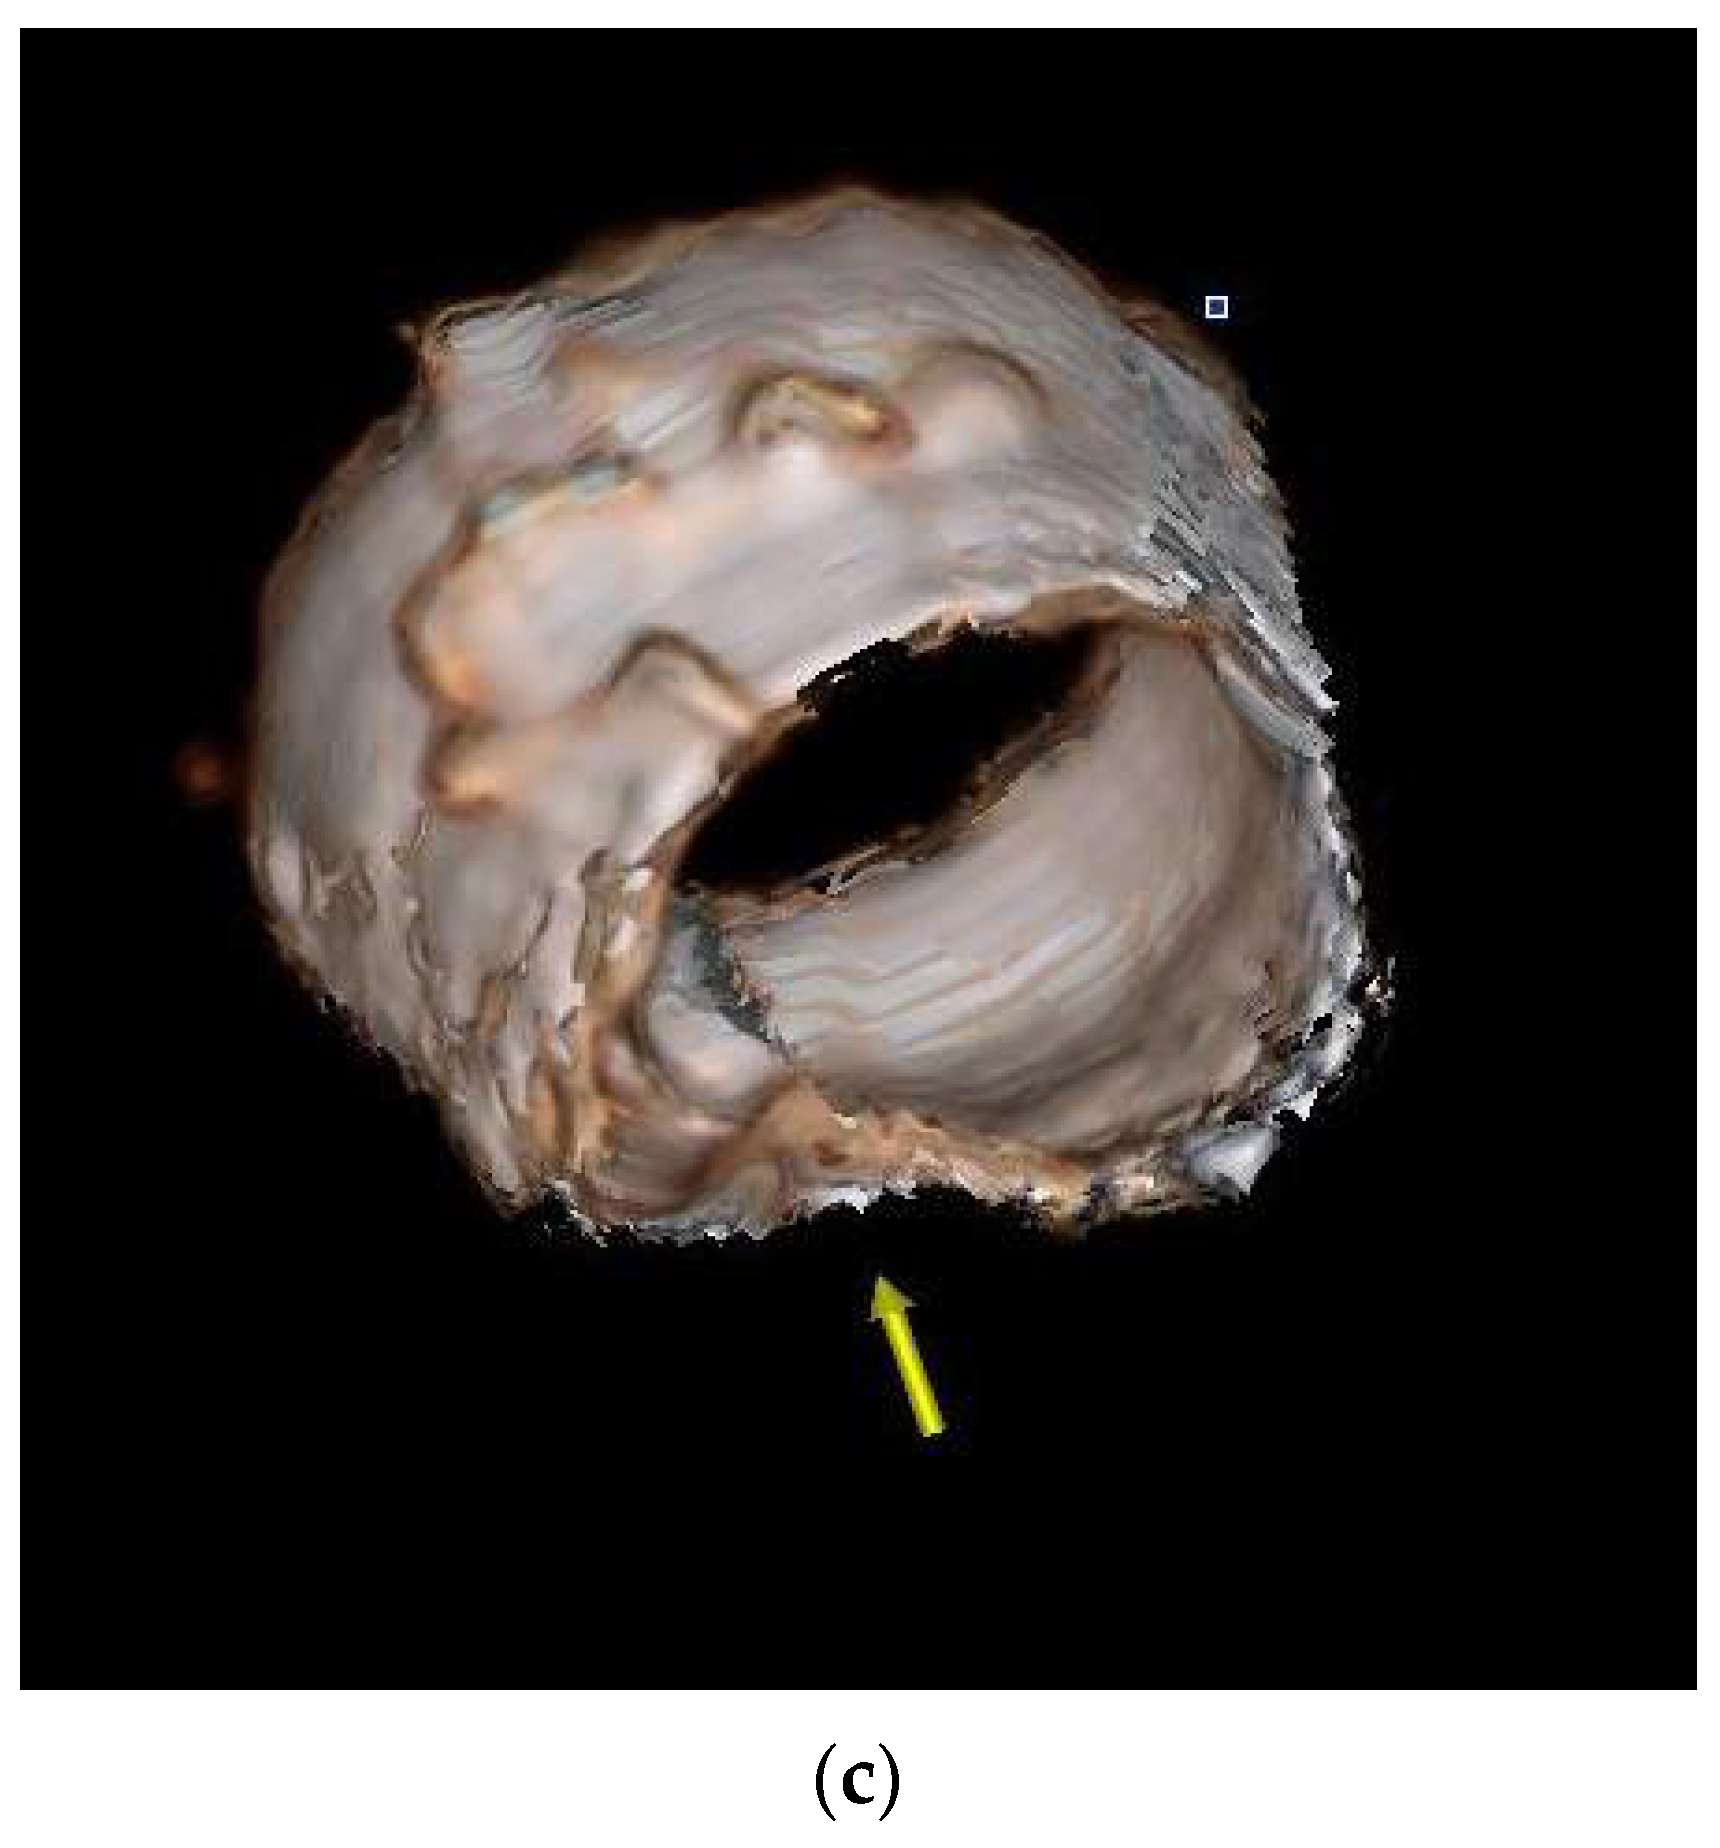

2.2. Case 2

2.3. Case 3

2.4. Case 4